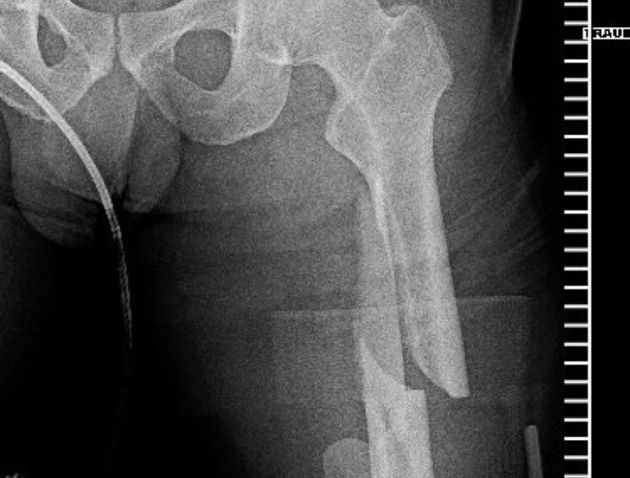

Vor ein paar Stunden wurde Steve deswegen im Palomar Medical Center Escondido operiert. Wie er selber berichtet, ist bei der OP an seinem Spiralbruch, linker Oberschenkel, alles perfekt abgelaufen.

An den Fotos unten kann man gut erkennen, dass der Knochen nun durch ein Titanstück und zwei Schrauben zusammengehalten wird. Den Moment des Sturzes hat Caballero auf Instagram hochgeladen. Den Clip findet ihr unter den Fotos.